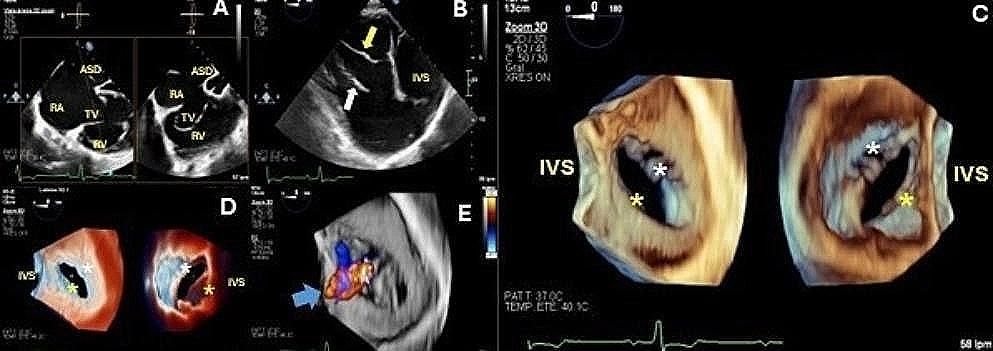

🫀 Essential: Imaging role in criss-cross heart diagnosis/approach—scoping review & cases at #IJCVI.

🌐

The role of imaging in the diagnosis and approach of criss-cross heart: a scoping review and case series

The International Journal of Cardiovascular Imaging - Criss-Cross Heart is a congenital cardiac condition characterized by the anomalous twisting of the ventricles relative to the atria during...

doi.org